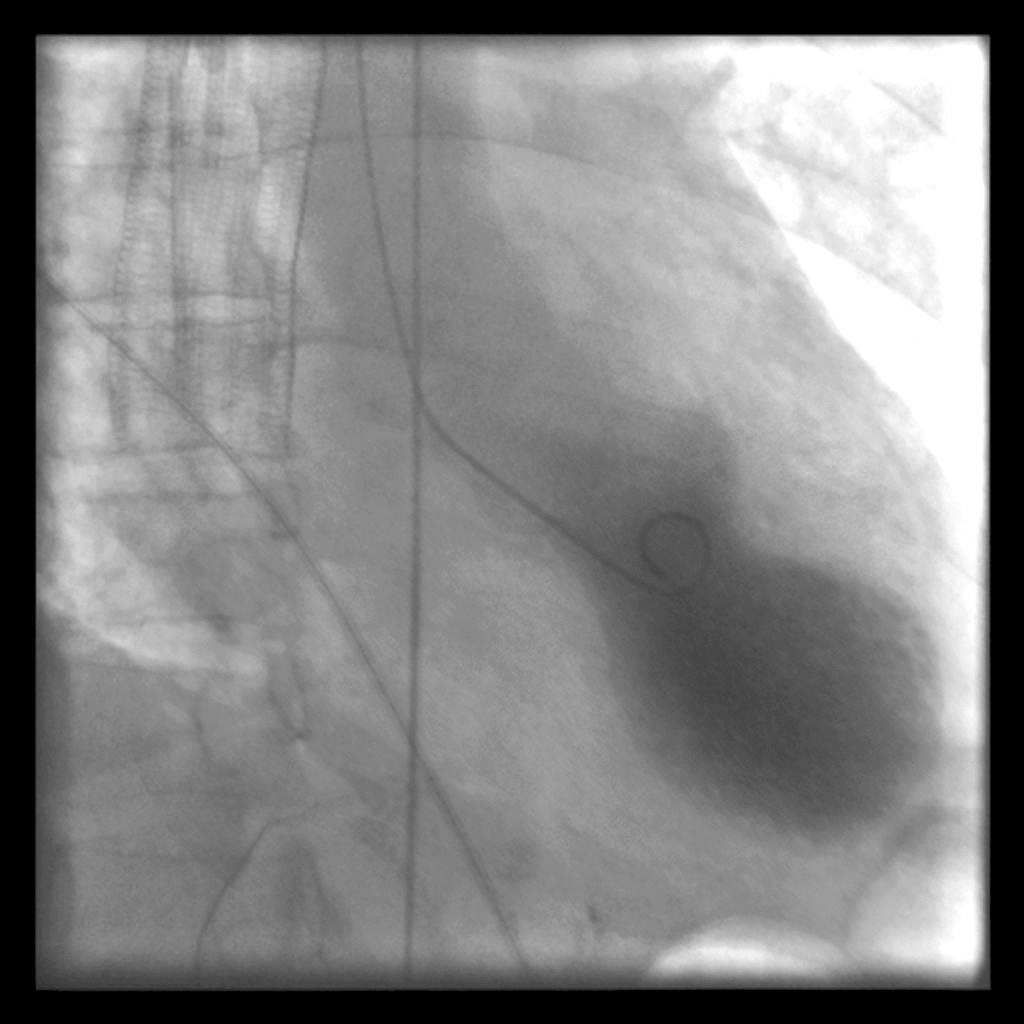

File:Takotsubo ventriculography.gif

| current | 02:28, 2 December 2015 | 1,024 × 1,024 (302 KB) | Alvarez13 (talk | contribs) |